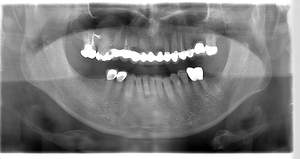

インプラント治療の症例2

レントゲン写真

- Befor

- After

口腔内写真

| 年齢 | 50代・男性 |

|---|---|

| 主訴 | 左上7番 左下5番7番 |

| 治療内容 | ・インプラント埋入 ※1:GBR(骨造成)・・・骨再生誘導法。骨の高さや厚みを人工骨や人工膜などを使用し再生する方法 |

| 治療費 | 合計:1,809,500円(税込) ■内訳 ・左上7番 ・左下5番7番 |

| 治療期間 | 左上7番約1年 左下5番7番約10ヵ月 |

| 治療方針 | 左上7番は昔他院で被せものをしており、被せものの中が歯ぐきの中まで虫歯になっていたため抜歯せざるを得ない状態だった。抜歯と同時に骨造成を行い、骨が出来るまで4ヵ月待ってからインプラントを埋入した。 ※2ポンティック・・・歯のない部分を補うダミーの歯。 |

| 担当者所見 | 元々金属の被せものが多く入っていたため、2次カリエス※3が多かった。今回は金属ではなく、ジルコニアを使用し、2次カリエスにならないよう、患者様にはブラッシング指導とメンテナンスの重要性をお伝えした。 ※3二次カリエス・・・詰め物や被せものを入れた歯が虫歯になること。 |